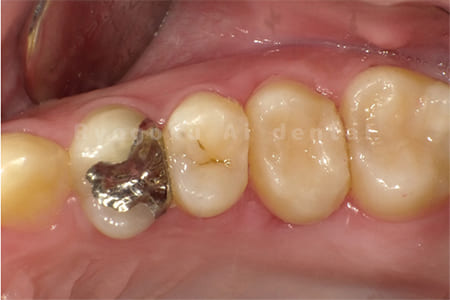

Case10

- 右下6番 重度カリエス

- 右下8を右下6へ移植に自家歯牙移植

- 治療期間

-

- 220,000円

右下の銀歯が外れかかっているとのことでご来院された患者様です。虫歯が大きく、かつ歯が割れており、保存不可能と判断し、親知らずの移植を行いました。

<リスク・副作用>

治療後、痛みや違和感、出血、腫れなどが出る事があります。喫煙者、糖尿病などの方の場合、歯が生着しない場合があります。